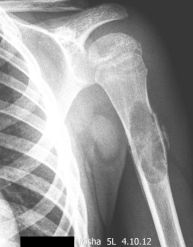

248. Просто киста?

Ребенок 5 лет.Травма накануне. Смущают линейные остеофиты по наружной и внутренней поверхностям. Уважаемые коллеги, пожалуйста, помогите разобраться.

Тип: Клиническое наблюдение

Область: Скелетно-мышечная система

Модальность: Rg

Дата: 05.10.2012 - 18:14